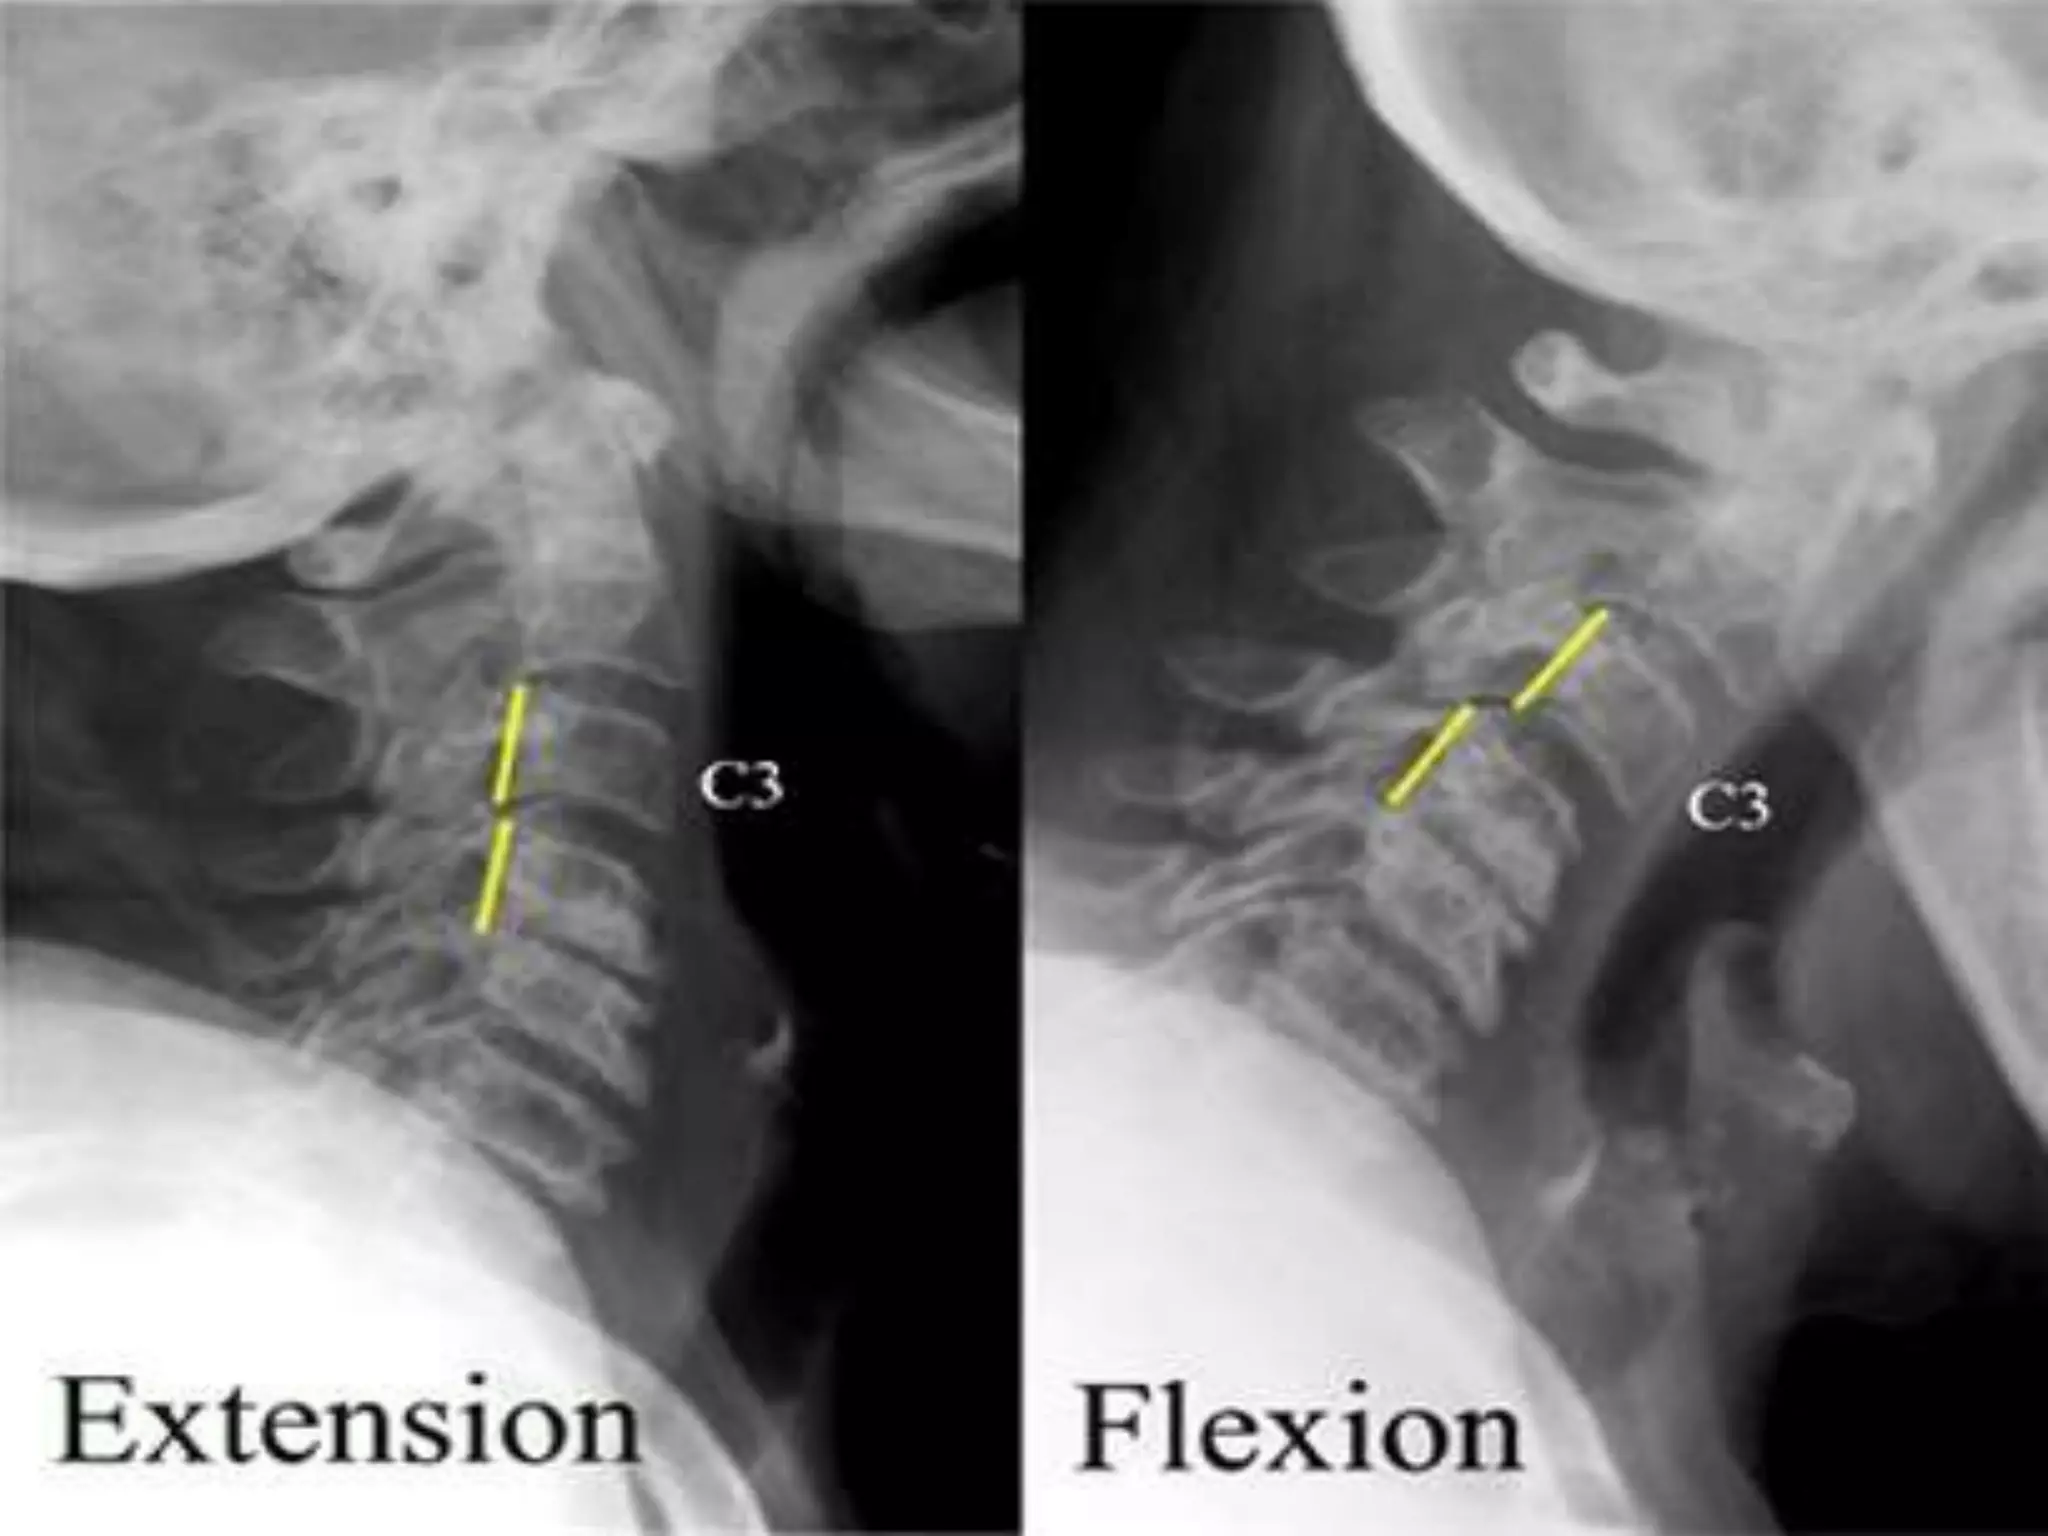

Extension and flexion x-rays.